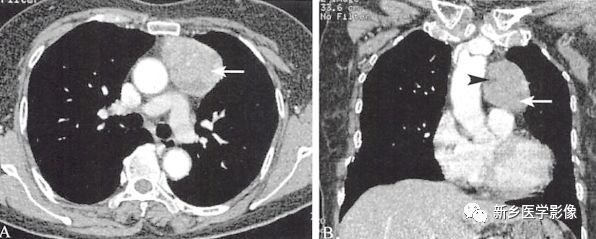

纵隔生殖细胞肿瘤之精原细胞瘤

553x251 - 95KB - PNG